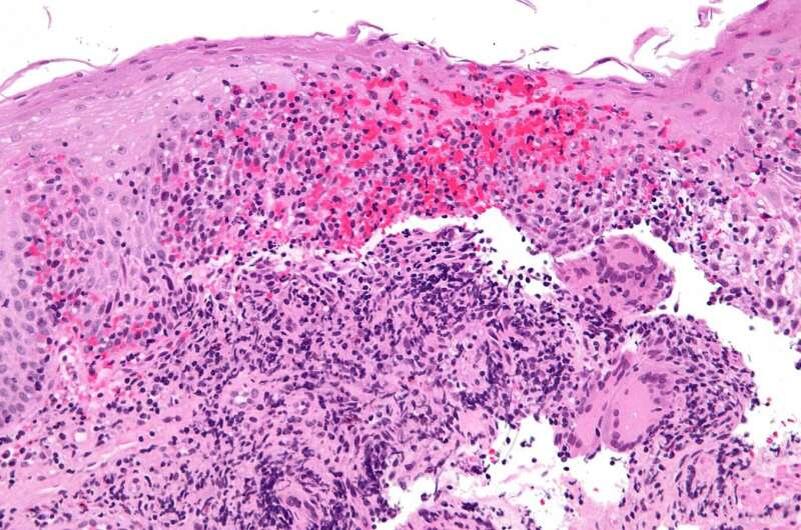

По всем ключевым точкам, включая эндоскопическое улучшение и так называемую «глубокую ремиссию», гуселькумаб оказался на голову выше. Особенно примечательно: впервые в истории лечения Крона один биопрепарат в лоб обошёл другой — и это не шутка.

«Даже несмотря на богатый арсенал биологических препаратов, устойчивое улучшение у пациентов с болезнью Крона до сих пор остаётся проблемой. GALAXI дал нам серьёзную надежду. Особенно приятно видеть не просто клиническое улучшение, а реальные эндоскопические признаки заживления слизистой».